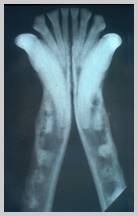

Root resorption (external) affecting

multiple mandibular premolars in the dog